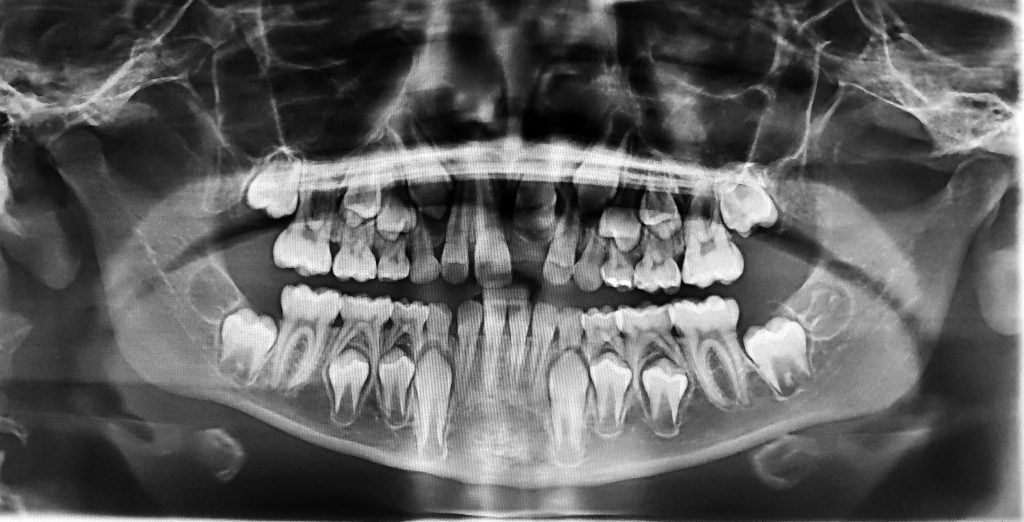

Las muelas del juicio son los terceros molares, que suelen erupcionar entre los 17 y los 25 años. En muchos casos, estas piezas no encuentran el espacio adecuado para salir correctamente, lo que da lugar a una erupción parcial o una inclusión dentaria (cuando quedan retenidas dentro del hueso o la encía). Esta situación puede derivar en infecciones, quistes, caries en los dientes adyacentes, o incluso en problemas ortodóncicos.

- Impactación dental, cuando la muela crece en ángulo o no erupciona por falta de espacio.

- Presencia de quistes o tumores odontogénicos asociados a muelas retenidas.

- Evaluación preoperatoria con radiografía panorámica o escáner CBCT.